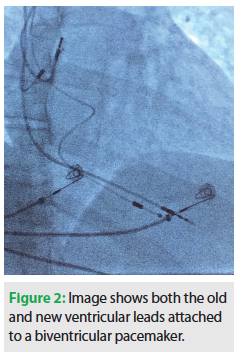

The old leads were evaluated and a visible insulation defect was identified in the right ventricular lead (Figure 1). The old right ventricular lead was repaired with a protective sleeve and attached to the left ventricular port of a biventricular pacemaker (Consulta® CRT-P, Medtronic, Inc.). New right atrial and right ventricular leads were implanted and connected to the device (the latter was connected to the right ventricular port). The new pacemaker was then placed into the pocket, which was irrigated with antibiotic solution and closed with deep and superficial suture. There were no complications. At her most recent follow-up several months later, the patient had no complaints and the wound was well healed.

Both right ventricular leads were performing within their specifications with acceptable thresholds.

This patient had complete heart block and was entirely pacemaker dependent with no underlying escape rhythm. As a healthcare worker, she knew that if the right atrial lead could fail, the right ventricular lead could also fail. It was her preference to replace both leads from the start, but we had no other evidence of right ventricular lead failure, and without that documentation, it was hard to rationalize the added cost of placing a new right ventricular lead. However, the patient’s apprehension regarding failure of the old right ventricular lead proved correct. During the procedure, it was immediately evident that the old right ventricular lead had a visible insulation defect. Although the defect was amenable to repair, the long-term stability following repair remained uncertain. In addition, the newly implanted right ventricular lead could dislodge or develop elevated thresholds, and thereby loss of capture, with a possible catastrophic result. Therefore, we utilized the old right ventricular lead with the newly implanted right ventricular lead, and attached both to a biventricular pacing device (Figure 2). This method provides a backup if the older lead fails.